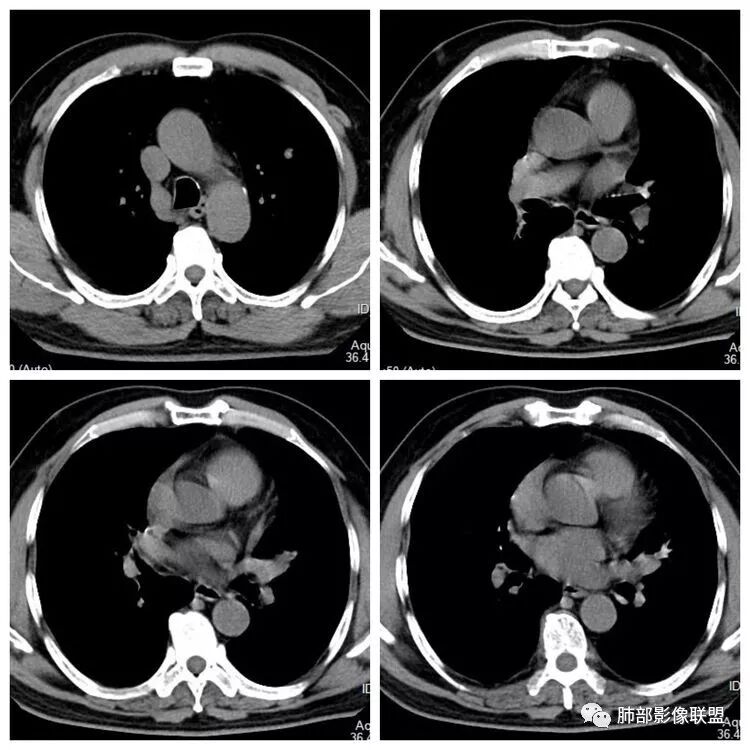

左下叶内前基底段实性占位堵塞支气管,强化较弱,考虑肺癌可能 ,小细胞?腺癌?

患者老年男性,“左肺占位”收入住院。查CEA轻度升高。胸部CT:左肺肺门占位并左肺下叶阻塞性,远端肺组织膨胀不全,增强可见轻度强化,内似见低密度灶。双肺多发类圆形结节,以左肺上叶尖后段为大,内可见部分钙化,边缘光滑、清楚。综合考虑恶性病变,鳞癌并转移可能大,鉴别腺癌、结核。

左肺下叶占位,左肺下叶前内支气管阻塞可疑(缺乏薄层),病灶有膨胀性,远端较内侧细,增强病灶强化不明显——乏血供病灶,病灶沿支气管生长,考虑恶性病变,左肺上叶可见小结节病灶,边缘光滑清晰,考虑转移瘤,综上所述考虑恶性病变,左肺下叶小细胞类癌可能,左肺上叶转移。

左上肺光滑圆形结节,内有钙化,密度不均,错构瘤;

左肺下叶结节支气管进入截断,远端肺不张,增强后坏死不均匀,肺癌明显,至于病理类型,鳞癌,小细胞,腺癌都有支持和不支持的地方,个人倾向于鳞癌可能,理由,纵隔淋巴结肿大不明显,远端阻塞性不张,支持小细胞的地方,坏死呈沼泽样,但纵隔无明显淋巴结肿大及冰冻表现。腺癌这种表现一般为低分化腺癌,但远端阻塞性不张及纵隔无明显淋巴结肿大不支持。

1.主病灶明显堵塞支气管,我觉得如果结核爬行,应该是外向内爬,这个我觉得是内向外堵塞,而且爬行的结核一般是肉芽肿,不是坏死,增强不会这么低,这个密度和强化比较符合一个坏死。最重要鉴别,结核的爬行是外向内,周围有树丫。这个是内向外,支气管堵塞且坏死明显,外周的堵塞性肺不张,没有树丫,所以主病灶考虑内向外,故结核爬行不太符合。而中央型腺癌不是没有,而是少,加上坏死这么明显,淋巴结转移不明显,故猜测鳞癌或者唾液腺肿瘤可能性比较大,因为后者也是支气管中央起源,强化比较弱的。腺癌和小细胞不太典型,类癌可以表现为支气管粘液栓,但是强化不够。

2.病灶在平扫时似乎软骨在病灶外,提示病灶位于支气管内?这个可以仔细观察一下。

3.至于那个结节。是否一元不太好说。给的不是薄层似乎,强化没有说。目测是一个比较光滑的病变,有微分叶。那套路就是判断与支气管血管关系看看。血管关系很重要,错构瘤是推移,psp是贴边,转移应该会有血供,血管会增粗,这个需要细节。孤立结节疾病谱有错构瘤,psp,肺本身另外一个肺癌,转移,结核球。也可以从这个病灶入手

初学者:这个结节里面点状高密度究竟是血管还是钙化,视频看不清楚,大家可以讨论一下。很有帮助下面这个图可以看到病灶整体有彭隆以及强化不均血管如果给我重建一下就好了,如中央钙化,强化弱,又血管推移,边缘这么光滑的又钙化,一般概率上良性的错构瘤最多,转移保险起见要排一排。

3.左肺上叶另见孤立结节影,边界清楚光整,中央钙化,未见脂质密度特征。

左肺上叶孤立小结节影未见异常强化。

7.左肺上叶孤立小结节影中央钙化可见于肠道肿瘤,但更多见于错构瘤,或是结核球。